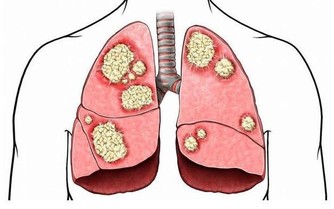

如果攝入大量的蛋白質和脂肪類的食物,在腸道內停留時間過長,可產生大量的毒素和致癌物質,甚至導致癌症的發生。

• 癌症:日本科學家指出,吃得太飽會造成抑制細胞癌化因子的活動能力降低,增加患癌機率。